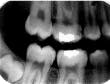

Overlap of contact surfaces

Perhaps the most common error is the overlapping of contacting surfaces (see Radiograph 1). When this occurs, the interpretation of caries is difficult at best. At worst, depending on the degree of overlap, interpretation often becomes virtually impossible.

The overlap is the result of incorrect horizontal angulation. With the paralleling technique, improper film-holder placement can be the cause. A simple adjustment in the film-holder`s position places it parallel to the facial surfaces of the teeth being exposed.

But the overlap can also be the result of errors in the angle of projection either mesiodistally or distomesially. When the horizontal plane projection is directed from mesial to distal, the resulting larger areas of overlap appear in the posterior portion of the film. Conversely, if the larger overlap appears in the anterior portion of the film, the horizontal plane of projection was directed distal to mesial.

To change this, place the film parallel to an imaginary line that is parallel to the facial surfaces of the teeth. The plane of the positioning indicating device/cone (PID) should then be parallel to this line and the film together. To determine the degree of overlap, use this general rule: If the overlap covers more than one-half of the enamel`s width, the degree of incipient decay and etchings are difficult to determine, and major technique problems need to be addressed.